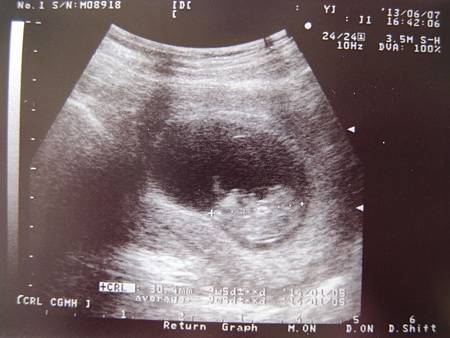

6/3  9W1D

今天在園所有抱恩傑餵奶,再加上他被咬的事情有點壓力,肚子悶悶的腰很酸,到廁所一看就發現又出血了,偏鮮紅色,馬上通知老公然後衝到國泰去,但卻因為衝到國泰都已經掛滿號,只好改到謝祖柏看診了,到謝祖柏打安胎針,回家後發現有點小血塊讓人緊張,照超音波的時候醫生忽然就說來聽一下心跳,然後就聽了,北鼻的心跳155醫生說正常,超音波看起來也都還好,不過記得之前國泰的醫生說10周前最好不要聽心跳,因為能量太大會傷到小孩,那現在才九週而已ㄟ,會不會傷到啊?!好害怕喔!今天看的超音波裡可以更清楚看到北鼻了,小小的手腳動來動去的,我有問醫生是北鼻自己在晃動還是因為在羊水裡,羊水晃動讓他看起來在動,醫生說是北鼻自己在動喔!好特別的感覺喔!感覺北鼻很好動的拼命擺動著手腳,是要告訴我他沒事很健康嗎?嗚~ 又想哭了........

昨晚沒睡好一直被蚊子騷擾,早上不到六點就醒了,切了一顆芭樂吃,約八點有排便算軟便,快八點半時外面傳來的油煙味整個讓我大吐,那種通過喉嚨很酸的感覺非常不舒服,孕吐當中又結合脹氣要排出來的氣體一起哽在喉頭差點喘不過氣來,一種要吐又卡住的感覺,一瞬間以為要死掉了,後來終於吐出來了.下午看醫生照超音波,確定北鼻現在的活動力良好,心跳也正常,也是有看到北鼻在擺動四肢,醫生說洗頭洗澡確實會流血,因為做的動作很多就會造成壓力,建議讓別人幫忙洗頭,並且臥床少走動,太常走動拖住子宮的五條肌肉就會拉扯,子宮也會壓迫神經所以才會覺得抽痛,反正躺就對了